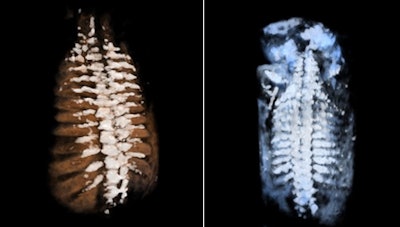

It is a great advantage to diagnose fetal skeletal dysplasia with 3D/4D technology because bone mineralization can be assessed and it is possible to compare bones (e.g., the spine with the skull bone and lavage bone), according to Dr. Peter Conner, PhD, of Karolinska University Hospital in Sweden. With 4D sequences, the fetal movement pattern and soft tissues can be assessed and, hence, malalignments can be diagnosed. Furthermore, with 4D it is possible to see fractures in both the lavage bone and ribs by using skeletal view visualization. In this mode, the skeletal structures are enhanced and soft tissues are suppressed.

A combination of better usage of 3D technology and knowledge of 3D technology in skeletal dysplasia will make it possible to correctly assess and diagnose many skeletal dysplasias in the first trimester. This is a major improvement, as most skeletal dysplasias are not currently diagnosed until the second or third trimester in families without a known family history of the condition, according to Conner. Adaptive volume enhancement technology, which suppresses unwanted signal such as noise/speckle, could also potentially facilitate the early diagnosis of skeletal dysplasias.